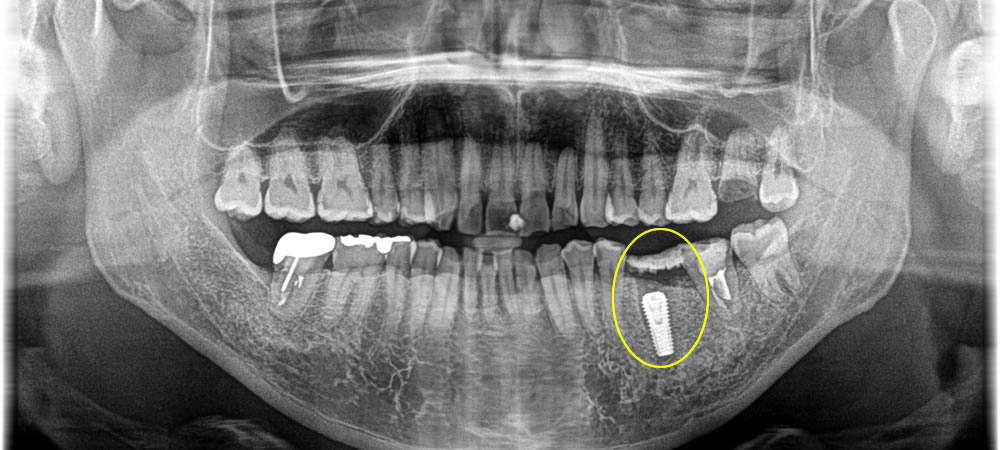

インプラント手術の実施

抜歯した部分の歯肉を切開し、インプラントを埋入しました。骨の損傷を補うため、骨造成も同時に行いました。

上部構造の装着・治療完了

インプラントと顎骨が結合したことを確認した後、型取りを行い、上部構造を製作しました。その後、完成した上部構造をインプラントに装着し、咬み合わせを調整して治療完了となりました。

インプラント埋入後は他の歯と変わらずしっかりと固いものも噛むことができ、見た目もキレイで審美的にも大変満足していただいております。